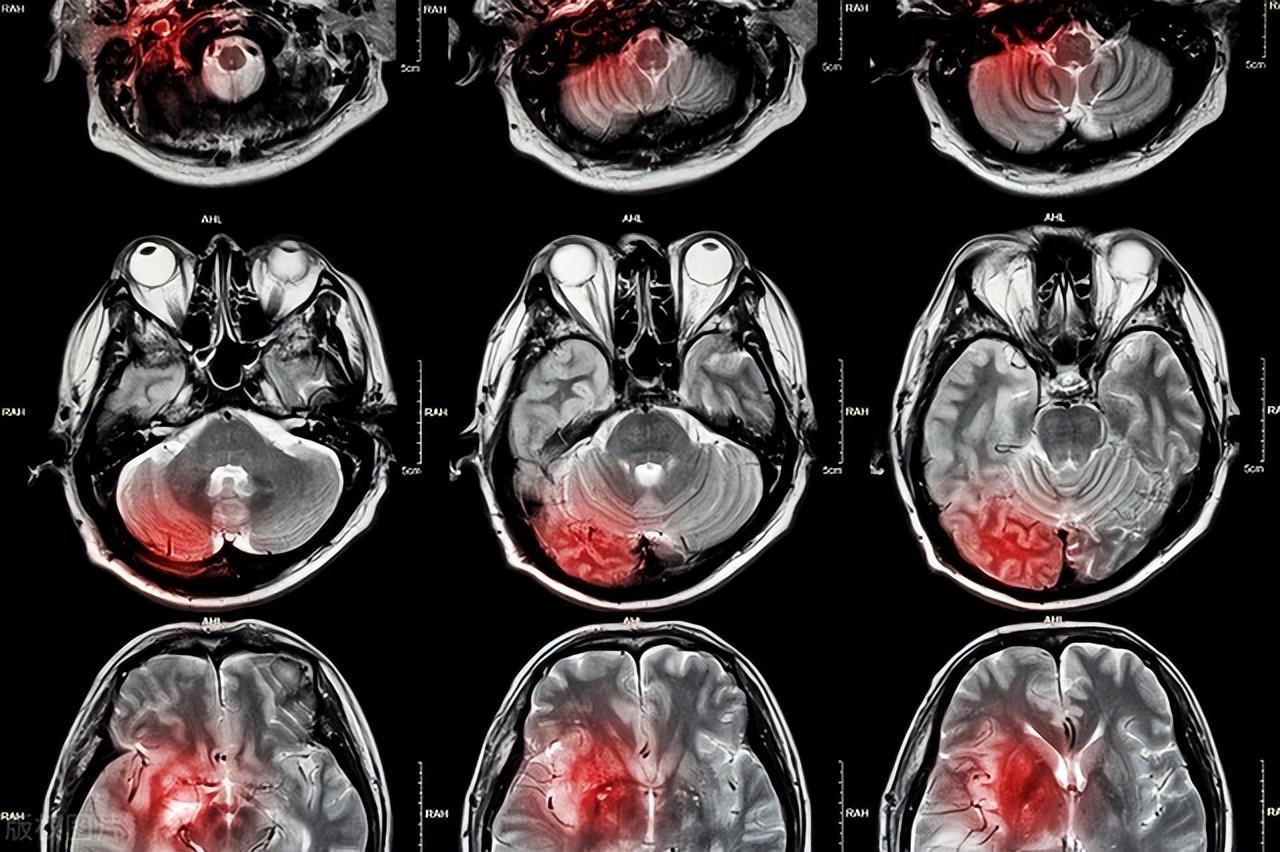

说到脑梗,相信大部分的人的感觉就是,经常在新闻上看到,也很害怕,但偏偏就是觉得不会发生在自己身上,要知道大脑是我们身体中最重要的一大部分,大脑中有很多的中枢神经,它支配着我们身体的各个器官,我们四肢的行动轨迹都是由大脑发出的命令,可想而知大脑本就是我们应该更加保护的部位。

说到这或许有很多的人都好奇,难道这种疾病都没有什么征兆么,怎么就在工作的时候突然离世了呢?其实说突然也不突然,脑梗的前期都会在身上出现一些问题,只是很容易被人们忽略。

因此如果你发现自己无端或者总是出现头晕、头痛甚至有呕吐的感觉,那么就要注意了,可能是脑部的血管堵塞导致的脑供血不足,所以出现这种情况,建议最好要到正规的医院检查,避免疾病严重化。

手脚麻木是脑梗患者最常见的症状,我们都知道身上的血液都要经过大脑,而四肢是血液循环的末端,如果大脑出现短暂的堵塞,就很容易会导致四肢的供血不足,从而产生手脚麻木的情况。这时你就要格外注意了,很可能就是脑梗前期发作的症状,同样要到正规的医院去做检查。

如果在日常生活中出现舌根发硬,说话不清楚、流口水等情况就要注意了,很有可能是脑部血管的堵塞导致脑部的管理语言的中枢神经首都到影响导致的,不要小看这一症状,发现后尽早到医院最检查。